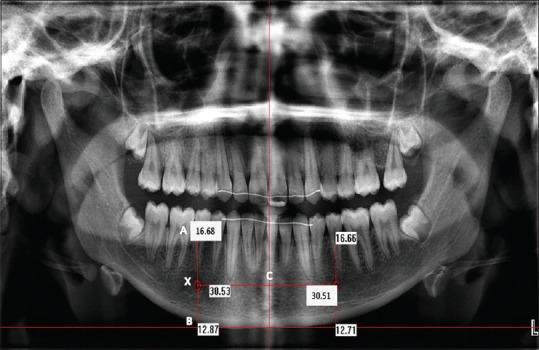

Digital panoramic radiographs of 250 patients were reviewed. The study population was divided into five age groups with 50 patients each. Radiographic position of mental foramen was evaluated in each radiograph based on three parameters. Measurements were taken in each radiograph using Planmeca Dimaxis pro version 4.4.0 (Helsinki, Finland). The collected data were subjected to statistical analysis using paired Student's t-test.

The mean distance of position of mental foramen showed a significant variation within the five age groups. In the first group, female patients showed an increase in mean distance of mental foramen position in relation to three parameters. From the second to fifth groups, male patient showed an increase in the mean distance of mental foramen position. The first and fifth group showed a reduced mean distance of mental foramen position when compared to other age groups.